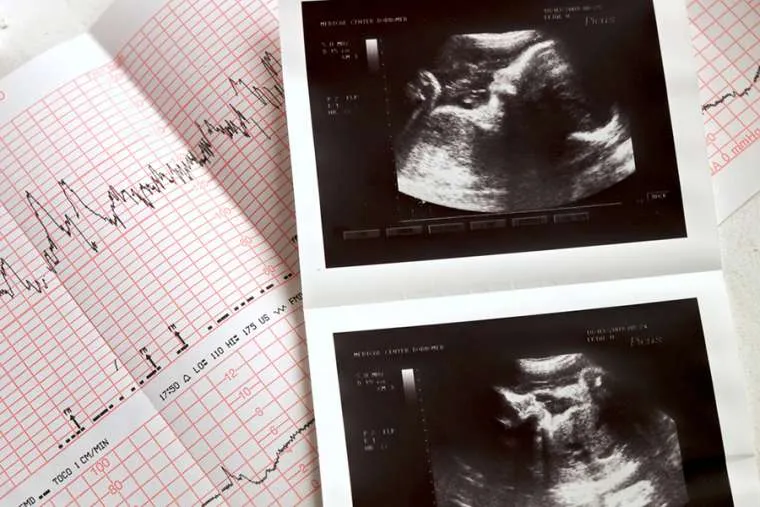

null / liseykina / Shutterstock.